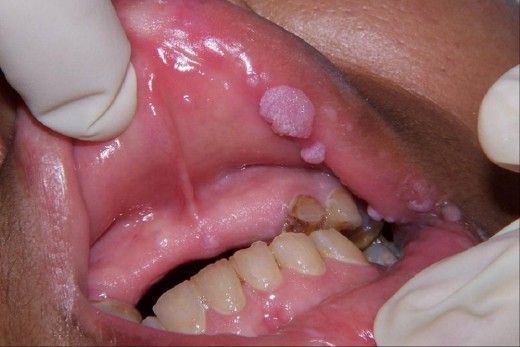

Sùi mào gà là một trong những bệnh lây truyền qua đường tình dục phổ biến, gây lo lắng cho nhiều người, đặc biệt khi sống chung hoặc ngủ chung với người bị bệnh. Câu hỏi đặt ra là: Liệu ngủ chung có khiến bạn bị lây sùi mào gà? Cùng khám phá 5 sự thật quan trọng dưới đây để hiểu rõ hơn.

Sùi mào gà do virus HPV (Human Papillomavirus) gây ra, chủ yếu lây truyền qua quan hệ tình dục không dùng biện pháp bảo vệ, bao gồm cả âm đạo, hậu môn và miệng. Việc chỉ đơn thuần ngủ chung nhưng không có tiếp xúc da kề da vùng nhiễm bệnh hoặc quan hệ tình dục thì nguy cơ lây nhiễm là rất thấp hoặc gần như không có.

Virus HPV cần môi trường ẩm và có tiếp xúc niêm mạc hoặc vết xước nhỏ trên da mới có thể lây. Do đó, chỉ ngủ cùng giường mà không có hành vi thân mật như ôm, hôn sâu, quan hệ tình dục hay dùng chung đồ cá nhân thì khả năng lây nhiễm là rất thấp.

Nếu bạn có vết trầy xước trên da và tiếp xúc trực tiếp với vùng da nhiễm bệnh của người khác, virus HPV có thể xâm nhập và gây lây nhiễm. Trong trường hợp ngủ chung mà có sự va chạm da vùng tổn thương với người đang có mụn sùi thì rủi ro lây vẫn tồn tại, dù không phổ biến.